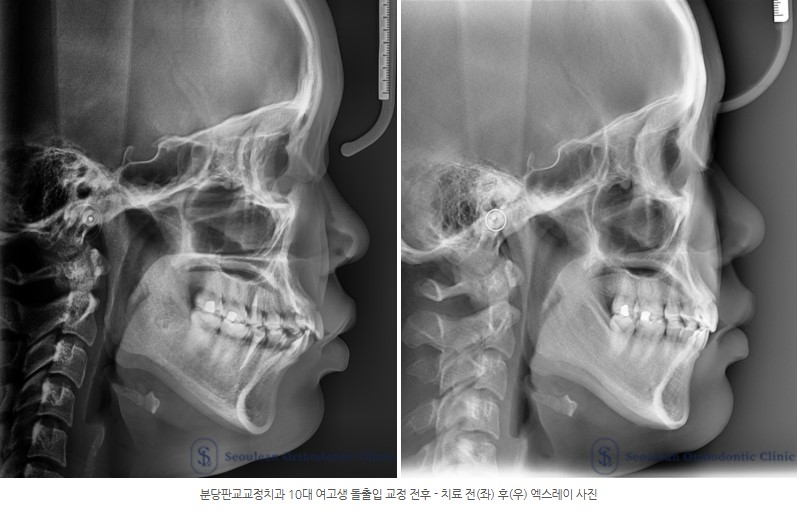

6. 교정치료 전후 변화

치료 종료 후 다음과 같은 변화를 확인할 수 있었습니다.

상·하악 전치 후방 이동으로 돌출감이 완화

자연스럽고 부드러운 입매 형성

균형 잡힌 안모